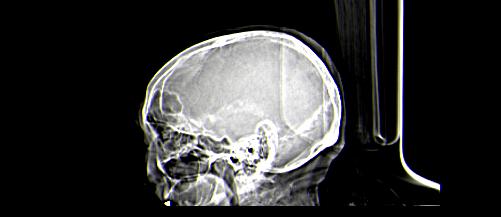

患者男性,67岁,头晕摔倒后来医院就诊,患者诉平时体健,否认有颅内病变史

定位:右侧脑室三角区扩大,呈球形,侧脑室颞角扩大,右侧脑室内占位:

定位:右侧脑室三角区扩大,呈球形,侧脑室颞角扩大。